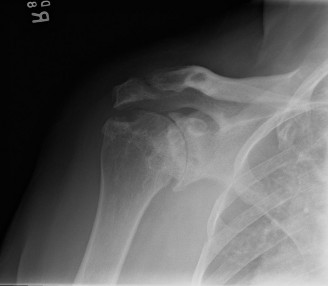

The challenges associated with treating an in-season athlete? CASE 12 A 28-year-old, recreational athlete presents to your clinic with shoulder pain and a history of multiple subluxations in the past. He describes a recent frank dislocation that had to be “popped” back in place on the field. His imaging is shown below (Fig. 2–34).

Figure 2–34

The correct answer is (A). The question describes a young, athletic patient with a history of multiple instability events, and as such, he is very prone to subsequent instability events. Although the initial treatment involves physical therapy, it is likely that this patient will require surgical stabilization. The image demonstrates a located shoulder with a small Hill–Sachs lesion and no significant glenoid bone loss, making capsulolabral repair the appropriate treatment option. For a patient with a failed capsulolabral repair or significant anterior bone loss (>20%), a Latarjet procedure is employed. A Remplissage (Answer C) is indicated for a large Hill–Sachs lesion, which is not seen on the image provided. A Putti–Platt procedure (Answer E) involves a vest-over-pants imbrication with the goal of shortening the subscapularis and anterior capsule. This procedure was historically used for anterior instability but has been replaced by more modern techniques as it causes a significant restriction of external rotation.